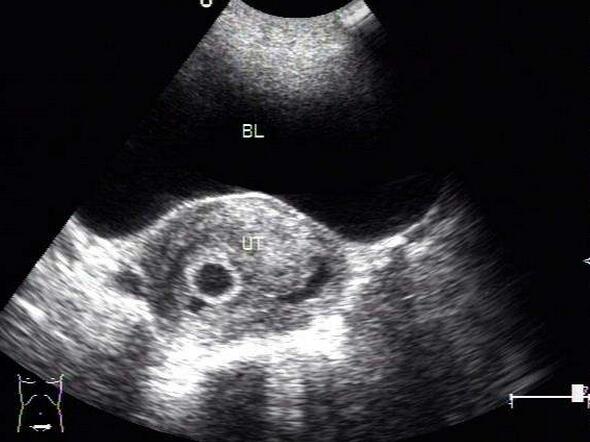

3、B超检测

B超检测是这几种方法里检测到的时间最晚的一种方法,但是也是更放心的一种方法,一般在停经40天左右能够看到孕囊,50天左右能够看到胎芽及胎心。如果当时检测不到,一般过一周后复查也能够看到。

在这里特别提示一下,停经40天并不是指的月经推迟40天,而是从最后一次来月经的那一天开始算起,40天左右。